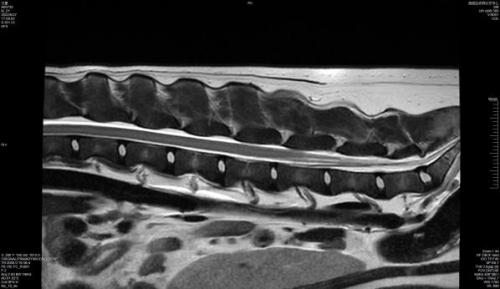

1.5T磁共振,疑难杂症“看得见”

为了更精确的诊断,芭芭拉宠物医院同时引入联影1.5T高场超导MRI。相比中低场强MRI,1.5T高场强不仅扫描时间更短而且图象质量更高,在MSK骨骼肌肉软组织成像、肝内脂肪含量分析等方面具有无法取代的效用,让更多疑难杂症无所遁形。

林祎医生表示,联影1.5T MRI的应用非常广泛。比如在脑部方面,可以开展MRA、SWI等序列联合评估脑梗情况;肝胆问题,则能通过MRCP技术来评估;肾性问题或泌尿系统问题,如果动物不适用于增强CT,也可以通过MRI开展MRU技术,不需要额外造影剂;扫描臂神经丛或腰骶神经丛,可以评估一些莫名的神经痛;十字韧带问题,MRI可以提供无创的检查技术;类PET MRI扫查,可以达到类似PET-CT的扫查效果,帮助评估肿瘤转移情况或体检筛查。

活动现场,林医生和大家分享了一些与联影1.5T MRI的精彩配合。比如有一只狗狗,主人的描述是一碰到屁股就尖叫。经过扫查发现其马尾神经出现高亮,因此造成剧痛。林医生强调,如此细的神经、如此小的压迫区域,如果是低场显影的话可能会非常模糊,但是通过1.5T MRI,则能非常清晰准确的看到问题所在。